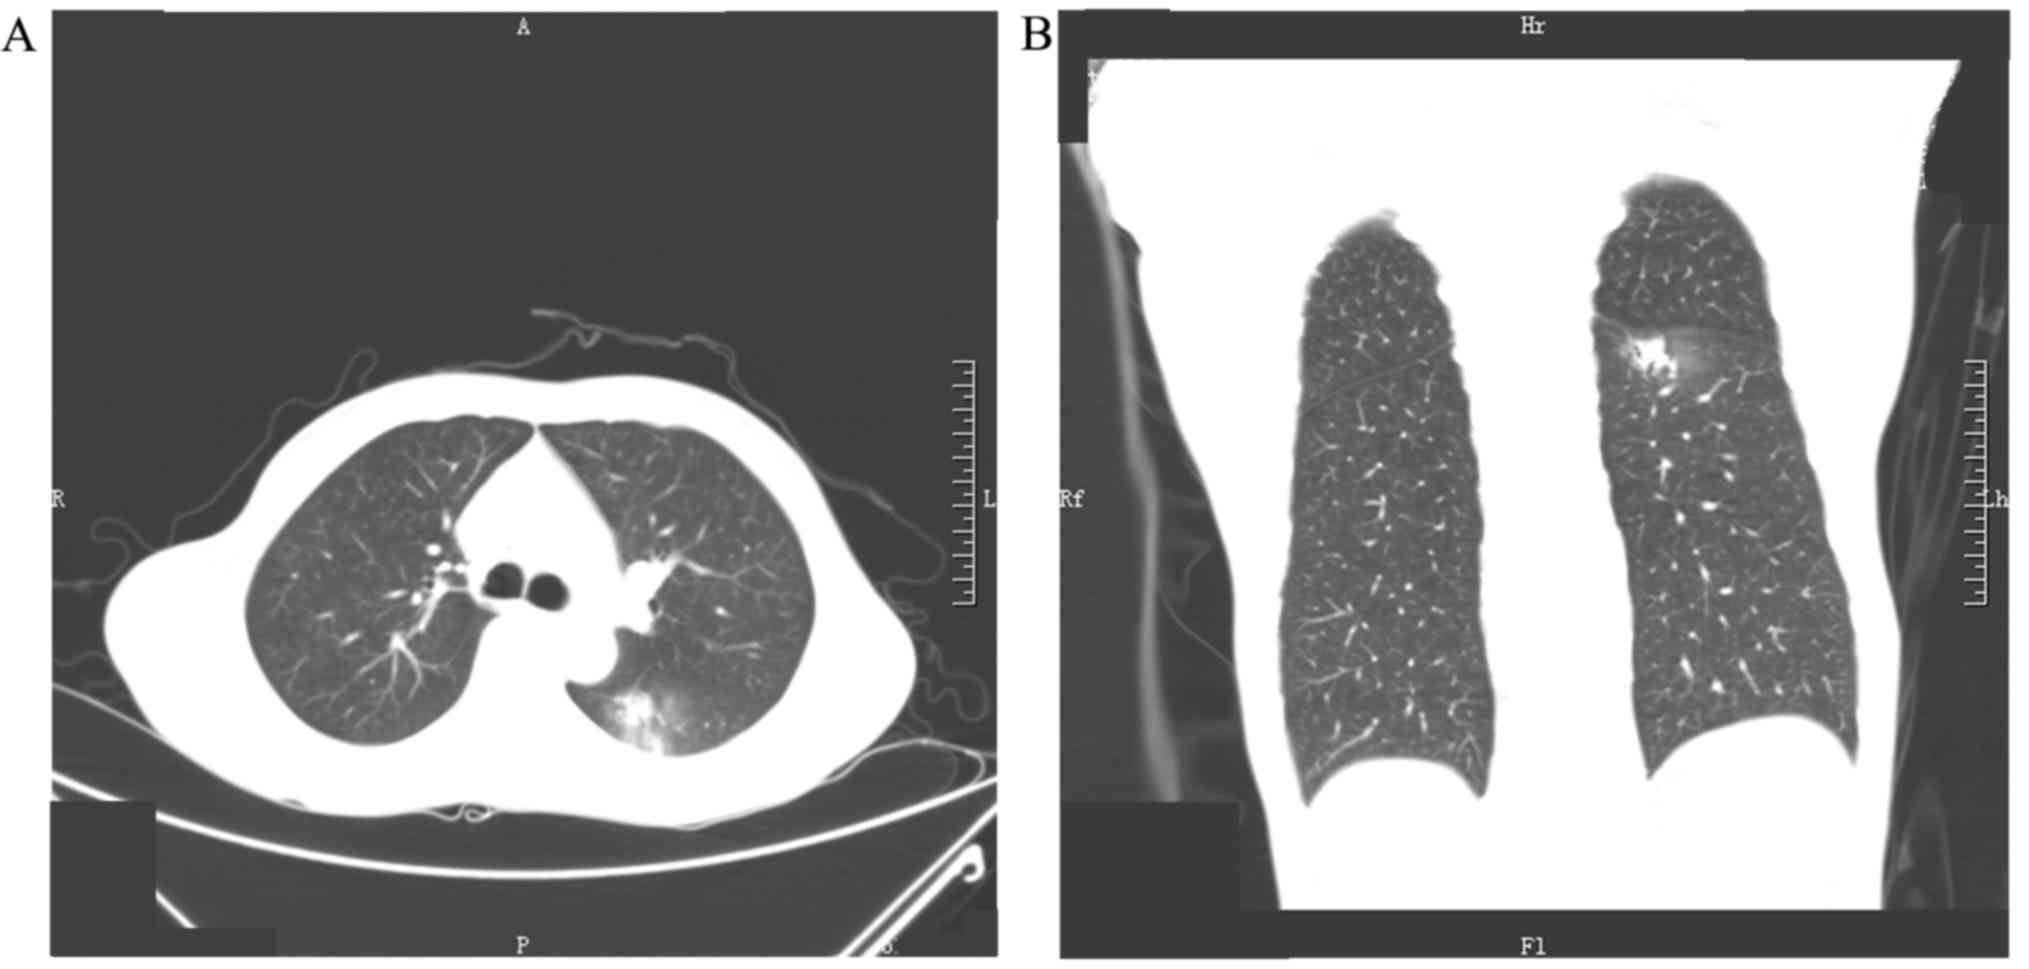

Figure 1.

Computed tomography images of GGN in the left lung at admission. (A) GGN in the lower lobe of the left lung, observed from axial view. (B) GGN in the lower lobe of the left lung, observed from coronal view. The postoperative pathology was adenocarcinoma. GGN, ground-glass nodule.